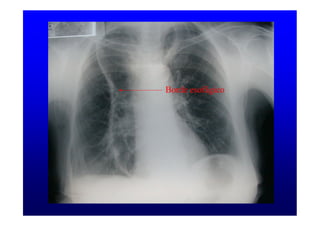

Borde esofágico